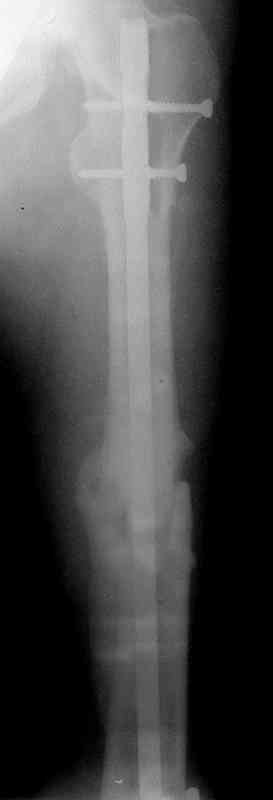

Сувалян Микаэл 01 Апрель 2007, 14:01

Вчера, когда написал свое сообщение, решил еще раз открыть фоторентгенограмму и убедиться в правильности своих суждений на счет общепринятого интрамедуллярного остеосинтеза. Попытка была безуспешна:)

Сегодня фотография открылась...беру свои слова назад: перелом явно в расширенном участке бедра. Целесообразней всего динамический блокирующий остеосинтез.

Ротации конечности у больного нет?

Есть ротация. Колено ушло внутрь.

История больного, о котором я говорил выше. Не удивляйтесь изложенному

материалу (выдержка из диссертационной работы).

Больной А., 28 лет, поступил в НИИ им. Н.В. Склифосовского 22.12.99 после падения на улице. Жалобы на боли в области левого тазобедренного сустава и левом бедре. Из анамнеза следовало, что 20.06 во время прыжка с парашютом у него возник закрытый оскольчатый перелом средней трети левой бедренной кости со смещением отломков, по поводу чего в одной из ЦРБ Московской области через 3 дня после травмы был произведен открытый интрамедуллярный остеосинтез штифтом типа Кюнчера.

Послеоперационное течение было гладким. Больной ходил при помощи костылей с дозированной нагрузкой на оперированную конечность.При осмотре в НИИ им. Н.В. Склифосовского через 6 месяцев после травмы:

левое бедро и левый коленный сустав несколько увеличены в объеме, отечны, пальпаторно определяется болезненность в средней трети бедра;

по его наружной поверхности послеоперационный рубец - рана зажила первичным натяжением. При измерении длины бедер обнаружено укорочение левого бедра на 4,5 см. На рентгенограммах этого бедра: ось конечности правильная, отмечается захождение основных костных фрагментов по длине, проксимальный конец штифта выступает слишком медиально и высоко относительно большого вертела, периостальная мозоль незначительна.22.12 - через 6 месяцев после операции, произведенной в ЦРБ, нами по поводу замедленно консолидирующего перелома левой бедренной кости с ее абсолютным укорочением под наркозом произведена операция: удаление штифта, закрытый блокирующий интрамедуллярный остеосинтез перелома левого бедра штифтом без рассверливания (UFN) длиной 40 см, диаметром 10 мм с блокированием только проксимальных отверстий (динамический остеосинтез). Наложен аппарат Илизарова на 4 полукольцах с целью удлинения укороченного бедра. Послеоперационное течение без особенностей. Ежедневно осуществляли дистракцию отломков на 1 мм. Через 3 недели после операции больной выпи-сан на амбулаторное лечение с продолжением дистракции отломков. В течение 1,5

месяцев дистракции укорочение левого бедра удалось полностью устранить. 22.02.00, т.е. через 2 месяца после повторного остеосинтеза, больному произведено дистальное блокирование штифта двумя винтами и демонтирован аппарат Илизарова. В течение 2 недель после операции больной ходил с помощью костылей, потом 2 недели с тростью. Опороспособность и функция оперированной конечности полностью восстановились через 4 недели после операции.

Фиксаторы удалены через 12 месяцев после операции, выполненной по поводу замедленной консолидации перелома бедра с его укорочением.